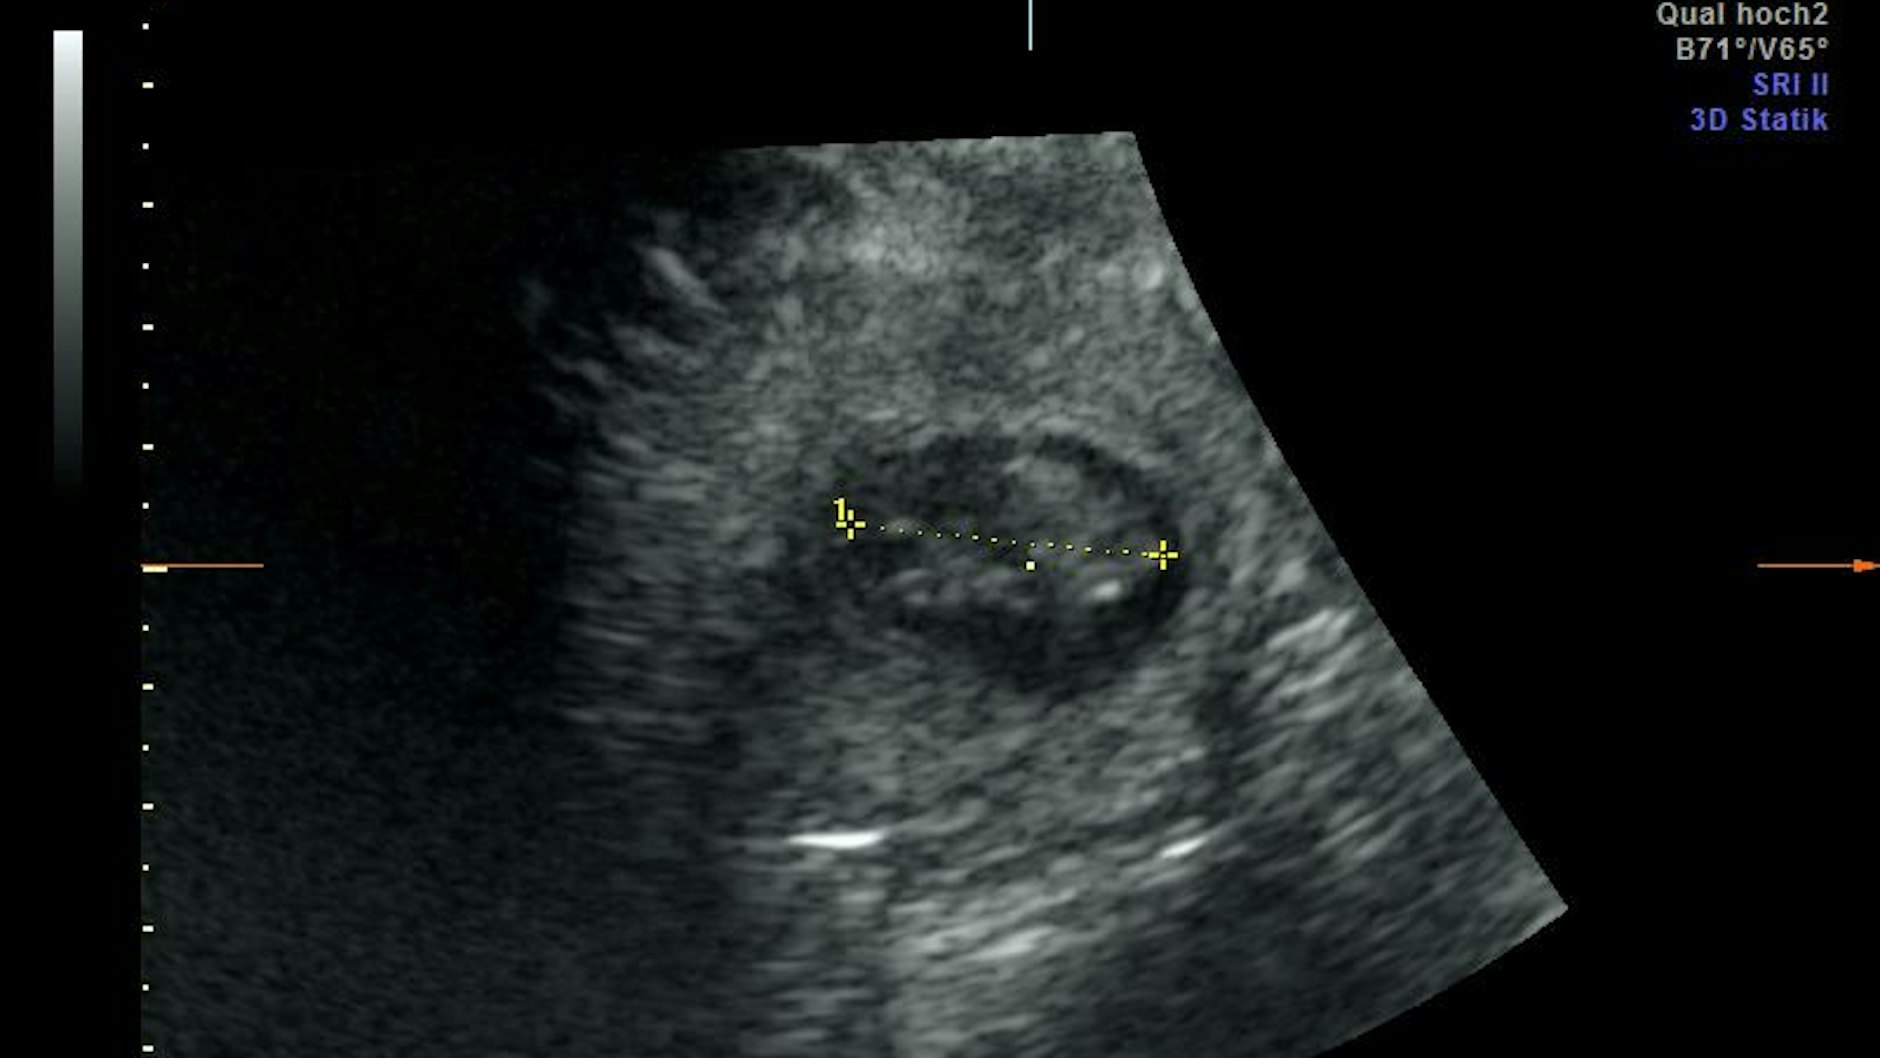

Am 11. August entdeckte man beim Ultraschall die beiden schlagenden Herzen der Embryos, die zu diesem Zeitpunkt etwa 2,5 Zentimeter groß waren. Eine weitere Untersuchung kurz darauf zeigte, dass die Embryos inzwischen auf etwa 6,5 Zentimeter angewachsen waren, wodurch die Gefahr einer Fehlgeburt stark reduziert sei, so Sicks.